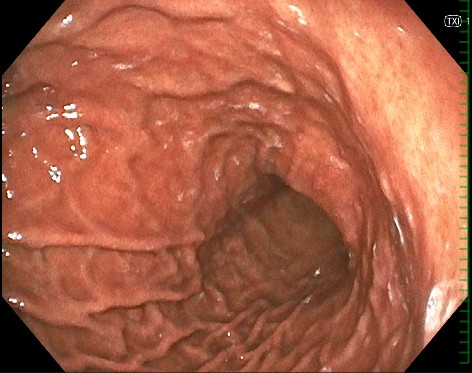

実際の内視鏡画像

胃カメラ

食道・胃・十二指腸に大きな炎症なし

ピロリ菌感染なし

がんにつながる異常もなし

→ 原因となる器質的疾患はなく、機能性ディスペプシアと診断